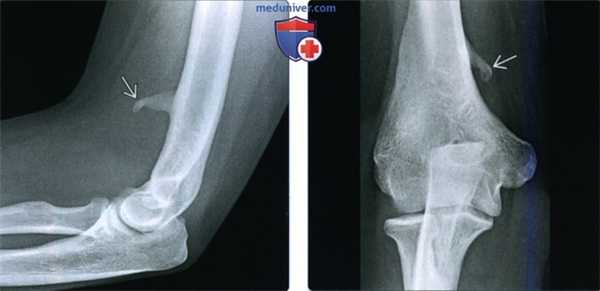

- Раздваивается непосредственно перед запястьем

(Слева) MPT Т2ВИ в режиме подавления сигнала от жира, аксиальный срез: у пациента с признаками синдрома запястного канала (СЗК) визуализируется гиперинтенсивный срединный нерв. Усиление сигнала на Т2ВИ и компрессия срединного нерва - убедительные признаки в пользу диагноза СЗК, но они не являются ни чувствительными, ни специфичными.

(Справа) МРТ Т2ВИ в режиме подавления сигнала от жира, аксиальный срез: у пациента с тендовагинитом сгибателей и СЗК определяется умеренная выгнутость удерживателя сгибателей в ладонную сторону. Наблюдается уплощенный, но обычной интенсивности, срединный нерв. (Слева) УЗИ срединного нерва, проксимальнее входного отверстия запястного канала, поперечная плоскость: наблюдается увеличение (15 мм 2 ). Площадь поперечного сечения нерва > 12 мм 2 , что предполагает СЗК. Обратите внимание на дополнительный признак в пользу СЗК-утрата волокнистой структуры нерва.

(Справа) УЗИ входного отверстия запястного канала на уровне крючковидной кости и кости-трапеции, поперечная плоскость: визуализируется уплощенный срединный нерв с умеренным утолщением удерживателя. (Слева) УЗИ срединного нерва, продольная плоскость: наблюдается умеренная деформация по типу «песочных часов» вследствие компрессии в запястном канале. Обратите внимание на нижележащее сухожилие сгибателей.

(Справа) МРТ Т2ВИ в режиме подавления сигнала от жира, аксиальный срез, пациент со снижением чувствительности латеральной стороны кисти и слабостью в большом пальце: определяется компрессия и гиперинтенсивность срединного нерва. Наблюдается отеки и умеренная атрофия короткой мышцы, отводящей большой палец.